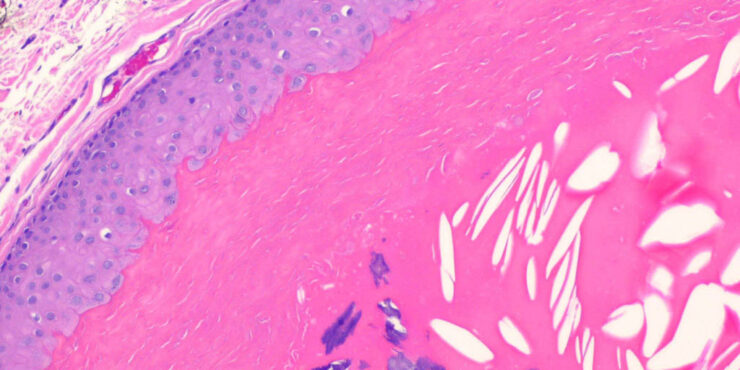

Pilar cyst = كيسة الشعر Pilar Cyst Pilar or trichilemmal cysts are clinically indistinguishable from epidermal cysts but differ from them in frequency and distribution. They are less common than epidermal cysts, constituting only about 25% of the combined material; about 90% occur on the scalp . Pilar cysts often show an autosomal dominant inheritance […]